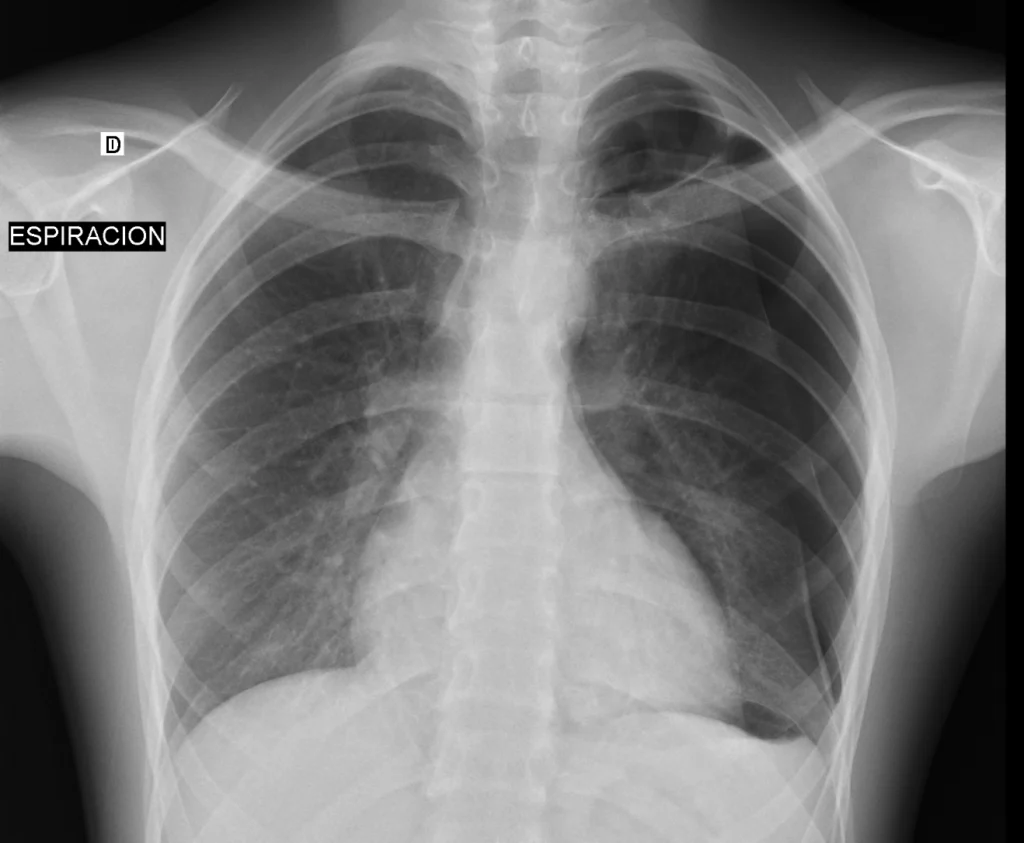

Rx de tórax PA en espiración. Se hace aún más evidente el neumotórax que puede ser infravalorado en la Rx en máxima inspiración, observándose en el sector superior pero también lateral del hemitórax izquierdo.

En este paciente joven, la clínica y el antecedente de un neumotórax un año antes orientaban a un diagnóstico presuntivo de neumotórax izquierdo. Sí bien era ya evidente en la proyección PA en máxima inspiración, en fase de espiración evidenció una mayor extensión del mismo. La proyección en espiración aumenta las posibilidades de identificar incluso neumotórax de pequeño volumen. Recuerda valorar la posición del mediastino: un mediastino desplazado hacia el lado contrario indica un neumotórax a tensión y requiere tratamiento urgente.